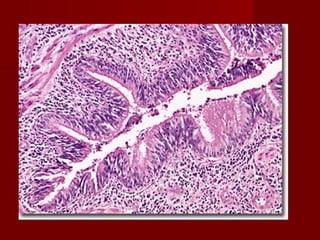

Patologi Anatomi

   Lumen Bronkus dilatasi (melebar) secara

patologis, ireversibel

   Terjadi obliterasi dari percabangan bronkus di

sebelah distal dari ujung yang sakit :

– Tidak dapat ditemukan kelanjutan percabangannya.

Bronkus seolah-olah terputus tepat sesudah atau tak

jauh dari pelebarannya.

– Ujungnya akan tertutup jaringan radang menahun

dengan hipersekresi yang mukopurulen sampai

dengan purulen betul

Patologi Anatomi  Lumen Bronkus dilatasi (melebar) secara patologis, ireversibel  Terjadi obliterasi dari percabangan bronkus di sebelah distal dari ujung yang sakit : – Tidak dapat ditemukan kelanjutan percabangannya. Bronkus seolah-olah terputus tepat sesudah atau tak jauh dari pelebarannya. – Ujungnya akan tertutup jaringan radang menahun dengan hipersekresi yang mukopurulen sampai dengan purulen betul